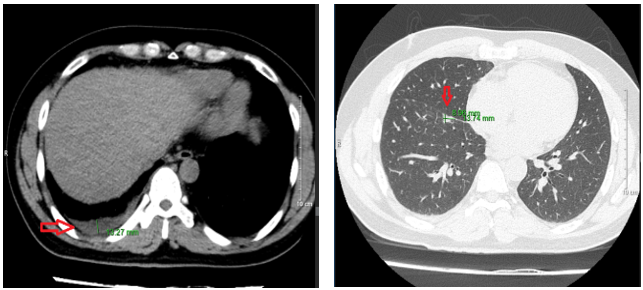

Chụp cắt lớp vi tính lồng ngực: Phổi phải nhu mô thùy trên sát rãnh liên thùy lớn có tổn thương dạng hang chứa khí kích thước 18x20mm, thành dày 8mm, bờ không đều. Nhu mô phổi còn lại có nhiều nốt đặc, nốt lớn nhất đường kính 13mm. Không thấy giãn phế quản – phế nang. Rãnh liên thùy phổi trái có nốt đặc bờ đều đường kính 2mm. Dịch khoang màng phổi phải dày 13mm.

Hình 1: Hình ảnh chụp cắt lớp vi tính lồng ngực: hình ảnh tràn dịch màng phổi phải và nhiều nốt đặc nhu mô phổi phải

– Chụp cắt lớp vi tính ổ bụng: Hình ảnh theo dõi u máu gan phải kích thước 18x20mm

– Chụp cộng hưởng từ sọ não: Hiện tại không có bất thường